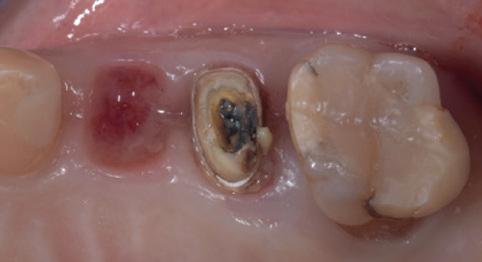

Imagine telling a new patient on the phone that the fee for their cleaning was $150.00 and then finding out when you meet them that they are a chronic smoker with advanced periodontitis in a mouth that hasn’t seen the inside of a dental office for forty years...

When we don’t pre-qualify the patient [on the phone] that because it has been a while between visits for them, that they may need extra visits to complete their cleaning, then one of the following three scenarios will occur:

• We rush the cleaning and fail to complete it properly; or

• We only do a superficial cleaning and so the patient receives incomplete treatment; or

• We defer necessary treatment to a later date and the patient carries on without knowing that they have active periodontitis inside their mouth.

And all of these scenarios are unsatisfactory and unprofessional results for our valued patients.